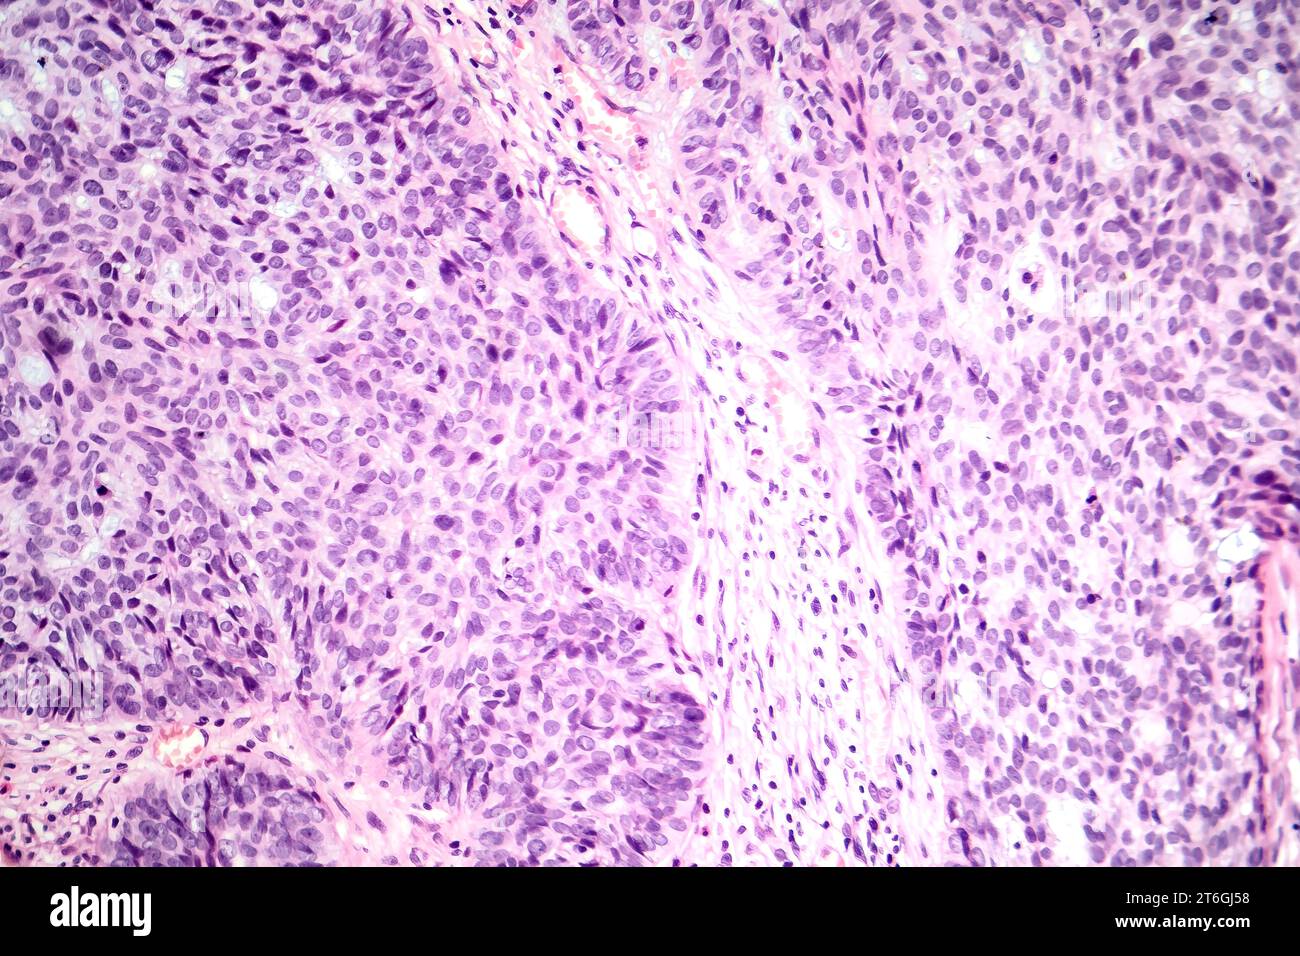

Basal Cell Cancer Cells. Sometimes, it can be mistaken for a harmless. basal cell carcinoma is a superficial, slowly growing papule or nodule that derives from certain epidermal cells. basal cell carcinoma (bcc, also called basal cell skin cancer, or just basal cell cancer) is most common type of skin cancer. basal cell carcinoma (bcc) is a type of skin cancer that can show up on the skin in many ways. the goal of treatment for basal cell carcinoma is to remove the cancer completely. Basal cell carcinomas arise from. Which treatment is best for. basal cell carcinoma is the most common form of skin cancer accounting for 90% of skin cancers in the. basal cell carcinoma is a type of skin cancer that causes a lump, bump or lesion to form on the outside layer of your skin. basal cell carcinoma (bcc) is the most common form of skin cancer and the most frequently occurring form of all cancers.

basal cell carcinoma is a superficial, slowly growing papule or nodule that derives from certain epidermal cells. basal cell carcinoma (bcc) is the most common form of skin cancer and the most frequently occurring form of all cancers. basal cell carcinoma is the most common form of skin cancer accounting for 90% of skin cancers in the. basal cell carcinoma (bcc, also called basal cell skin cancer, or just basal cell cancer) is most common type of skin cancer. basal cell carcinoma (bcc) is a type of skin cancer that can show up on the skin in many ways. basal cell carcinoma is a type of skin cancer that causes a lump, bump or lesion to form on the outside layer of your skin. Basal cell carcinomas arise from. Sometimes, it can be mistaken for a harmless. Which treatment is best for. the goal of treatment for basal cell carcinoma is to remove the cancer completely.

Basal Cell Cancer Cells basal cell carcinoma is a superficial, slowly growing papule or nodule that derives from certain epidermal cells. Sometimes, it can be mistaken for a harmless. basal cell carcinoma (bcc) is a type of skin cancer that can show up on the skin in many ways. Which treatment is best for. basal cell carcinoma (bcc) is the most common form of skin cancer and the most frequently occurring form of all cancers. basal cell carcinoma (bcc, also called basal cell skin cancer, or just basal cell cancer) is most common type of skin cancer. basal cell carcinoma is a type of skin cancer that causes a lump, bump or lesion to form on the outside layer of your skin. basal cell carcinoma is a superficial, slowly growing papule or nodule that derives from certain epidermal cells. the goal of treatment for basal cell carcinoma is to remove the cancer completely. Basal cell carcinomas arise from. basal cell carcinoma is the most common form of skin cancer accounting for 90% of skin cancers in the.